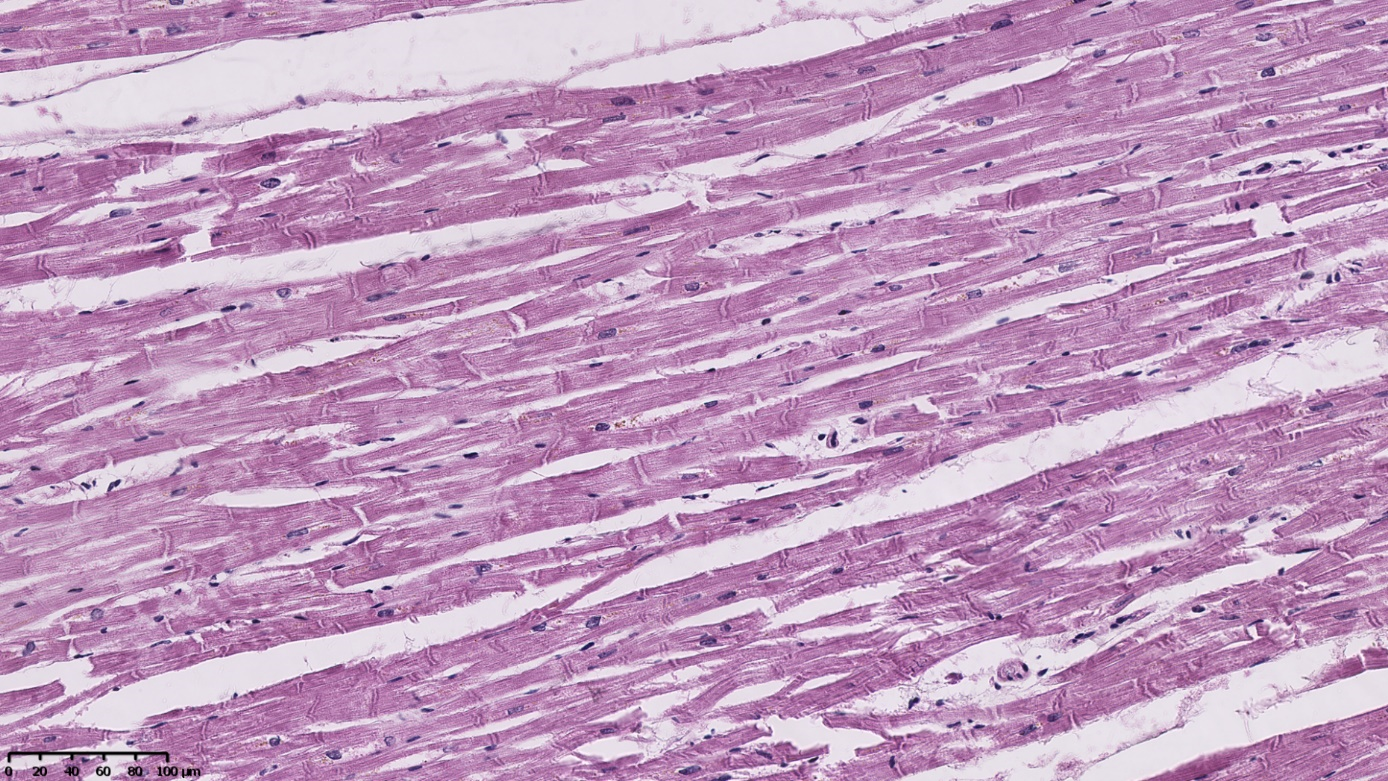

Investigating the cause and mechanism of death in cases of suspected fatal poisoning with new psychoactive substances (“legal highs”) is no different from classic post-mortem diagnostics in forensic medicine. There is no characteristic autopsy appearance in individuals poisoned with “legal highs”, therefore, in practice, biological material is most often reserved for complementary histopathological and toxicological examinations. This study aimed to assess the usefulness of microscopic examinations in assessing cases of fatal poisoning with new psychoactive substances. The authors’ analysis of the literature and the results of histopathological examinations of victims of “legal high” poisoning from their own practice at the Department of Forensic Medicine and Forensic Toxicology of the Silesian Medical University in Katowice revealed that the most common pathological or diagnostically questionable changes are observed in the heart, kidneys, and liver. In the heart, signs of early myocardial ischemia are often observed in the absence of atherosclerotic changes in the coronary vessels or changes such as muscle bridging along these vessels. Considering the relatively young age of the deceased, it is highly probable that the pathological changes observed are related to the use of “legal highs”, especially given their known cardiotoxicity. In the kidneys, signs of acute tubular necrosis (ATN) are most frequently seen. These signs are usually mild and overlap with autolytic changes, making their assessment difficult, especially since they may be periagonal (artifacts). Morphological changes in the liver typically represent focal hepatocyte degeneration. Only in one case did they demonstrate signs of active inflammation and developing fibrosis. The nature of the observed changes does not allow for a clear connection with the use of “legal highs”, as the same changes may be associated with metabolic disorders, obesity, alcohol abuse, or viral hepatitis. In summary, microscopic examination of internal organ samples collected during autopsies and post-mortem examinations of individuals who died from legal highs is only supportive, as there is no characteristic microscopic image that would allow for a definitive diagnosis. The extent of the patho-logical changes observed depends primarily on age and whether the poisoned individual was hospitalized. Infectious complications are often observed in cases of long-term stays in intensive care units (e.g., pneumonia associated with respirator therapy, signs of generalized infection).